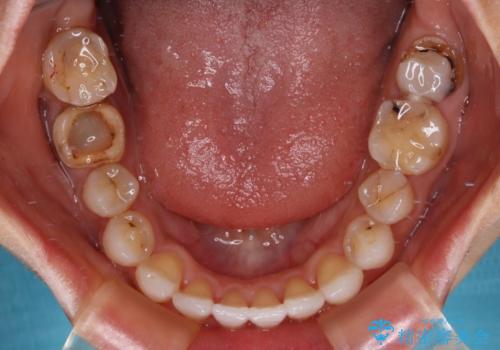

- 上下前歯の開咬とデコボコを気にして来院された患者様です。

開咬(オープンバイト)はインビザラインによる矯正治療がワイヤー装置と比べて圧倒的に有利であるため、インビザラインによる矯正治療を行うこととしました。

通院されなかった時期があって治療期間が長くなったり、奥歯に抜歯が必要な歯があったりと、治療は一筋縄にはいきませんでしたが、何とか治療を終えることができました。

今後はインプラント治療やむし歯治療を進めて行く予定です。